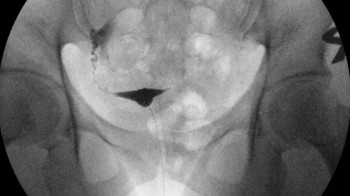

Rtg-urografija